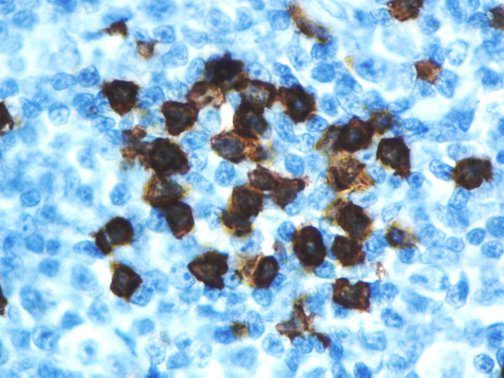

It is the ICU physician who is most likely to witness one of the deadliest manifestations of the abnormal immunological response, the cytokine storm syndrome (CSS). This response is also referred to by some as the cytokine release syndrome (CRS). CSS is characterized by continuous activation and expansion of macrophage and lymphocyte populations, which secrete large amounts of cytokines, causing the cytokine storm. This massive cytokine release is akin to hemophagocytic lymphohistiocytosis (HLH) disease, a syndrome characterized by initial unchecked and persistent activation of cytotoxic T lymphocytes and NK cells.

Clinical and laboratory manifestations of HLH include fever, enlarged liver and/or spleen, neurologic dysfunction, coagulopathy, liver dysfunction, cytopenias (i.e., low levels of erythrocytes, leukocytes, and/or platelets), hypertriglyceridemia, hyperferritinemia, hemophagocytosis, and eventually diminished NK cell activity as the immune system becomes progressively paralyzed. HLH can be familial (primary HLH) or secondary to another disease process (sHLH), such as rheumatic disease, in which it is referred to as macrophage activation syndrome (MAS, characterized by elevated ferritin).